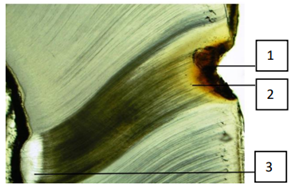

Em relação a dentina marque a alternativa INCORRETA.